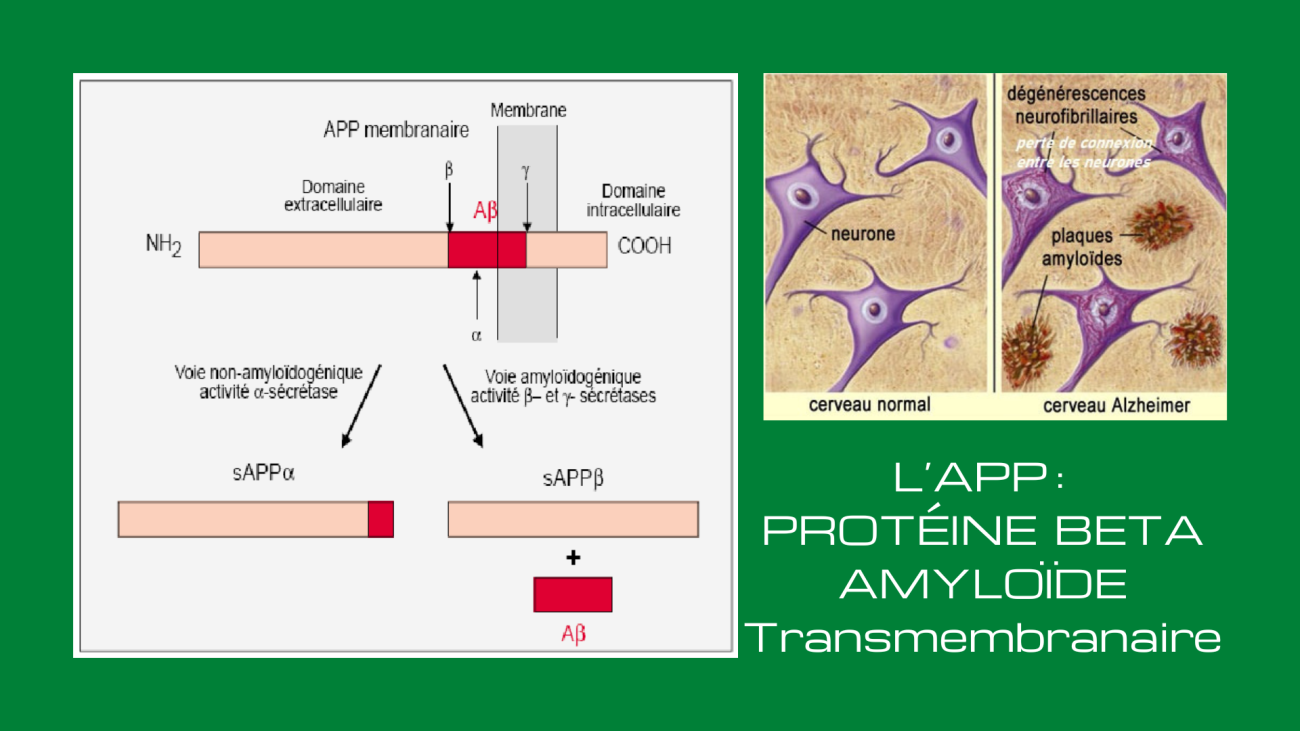

La Protéine Béta-Amyloide. L’APP est une protéine transmembranaire, c’est-à-dire située à travers la membrane des neurones. Elle est très présente dans le système nerveux central où on la retrouve à l’extrémité des synapses. L’APP, tout comme la bêta-amyloïde qui en est issue, est donc un composant normal de l’organisme. L’APP aide par exemple les neurones à croître, à survivre et à se réparer quand ils subissent des lésions.

Pour libérer la bêta-amyloïde, l’APP doit être coupée à deux endroits par des enzymes particulières. Les bêta-sécrétases vont d’abord couper la chaîne d’acides aminés de l’APP à une certaine distance de la membrane à l’extérieur de celle-ci. Puis, d’autres enzymes, les gamma-sécrétases, vont faire une autre coupure, cette fois à l’intérieur même de la membrane, libérant ainsi le peptide bêta-amyloïde. La longueur de ce peptide bêta-amyloïde est variable, allant de 38 à 42 acides aminés. Les deux formes principales sont toutefois celles à 40 et 42 acides aminés, la seconde étant celle qui a tendance à s’agglutiner pour former les plaques amyloïdes responsables des dégénérescences neurologiques, notamment la maladie d’Alzheimer.

Les enzymes responsables de la coupure de l’APP en peptide amyloïde beta (ou Aß) ont été découvertes en 1999 comme étant des sécrétases, qui agissent sur la partie transmembranaire de l’APP. L’APP peut donc être clivée par trois complexes protéolytiques appelés α-, ß- et γ-sécrétases. Il existe deux voies différentes qui sont caractérisées par des clivages de types différents.